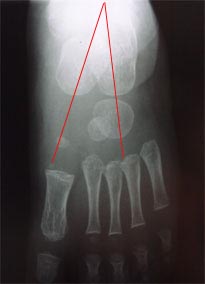

La radiographie du pied bot varus équin idiopathique avant traitement montre que l’axe du calcanéum et l’axe de l’astragale sont presque parallèles.

Normalement ces axes se croisent sur la radiographie de face ou de profil.